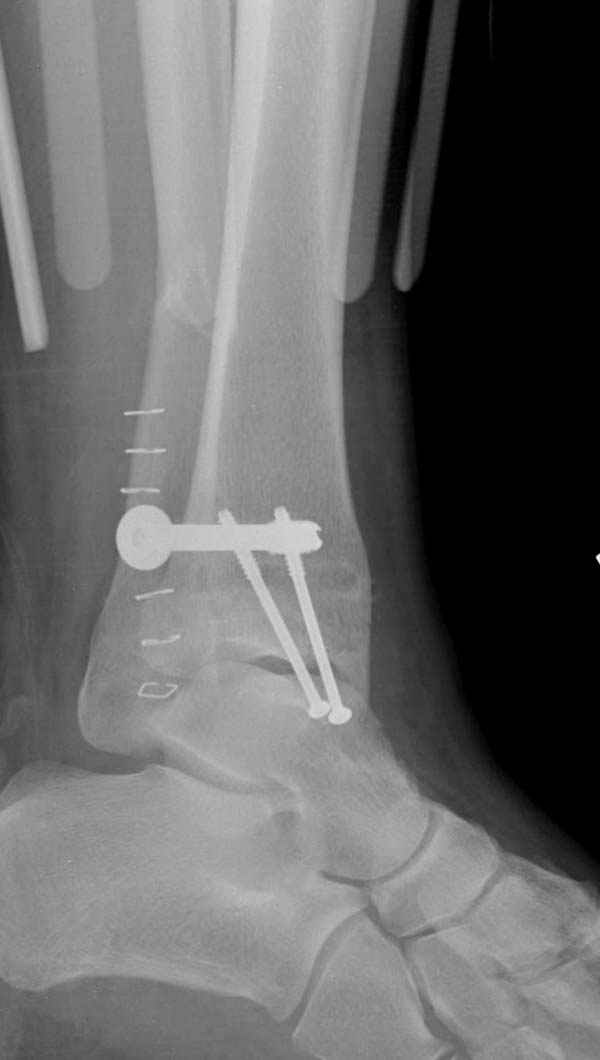

Ниже рентгенограммы

15 ноября прямой

|

15 ноября боковой

15 ноября трехчетвертной

Риторический вопрос - в каком руководстве рекомендован такой способ остеосинтеза наружной лодыжки?

Очевидно, такой результат операции был запрограммирован. При невосстановленной длине и практически нефиксированной малоберцовой кости (этот кортикальный винт - как карандаш в стакане), при неустраненном подвывихе, невправленной и тоже нефиксированной внутренней лодыжке нет стабильной вилки сустава. Если такую операцию сделать даже сразу, а не через 4 месяца, то результат ожидаем

Вариант с артродезом уже обсудили. Хотя, после увиденых снимков, пессимизм насчет восстановительной операции у меня, например, несколько уменьшился. Особенного уж какого-то остеопороза не видно даже на январских снимках. Можно черед мини-доступы убрать винты, аппаратом вправить малоберцовую кость, устранить подвывих стопы. Ну а дальше фиксировать малоберцовую пластиной сзади. А может, и напряженной Y-спицей попробовать - Анатолий Федорович, как Вы полагаете? Внутреннюю - то, что осталось, если уже не получится сделать спицами и проволокой, то что-то типа пластики дельтовидной связки. А может, и не трогать ее вовсе... В общем, выбор непростой,

много факторов надо взвесить.

Если до сих ничего не сделано, с артродезом сустава в данный момент я бы повременил, на выставленных январских снимках хорошо сохранившийся сустав, а в "мортиз" (трехчетвертной) и на боковых снимках не менее 5 мм укорочение малоберцовой кости. Косые переломы лучше фиксировать пластинами, как то мы разбирали случай, где было отмечено, что это закон "таранная кость всегда следует за малоберцовой".

В данном случаи я бы уговорил больного на реконструкцию, для этого после удаления шурупов, спереди очистить от рубцов синдесмоз, несросшуюся наружную лодыжку - остеотомия по линии перелома и компрессирующий (lagging technique) кортикальный шуруп 3.5 мм по поперечнику остеотомии. Следующий этап - восстановление длины малоберцовой за счет удлинения, сделать поперечную остеотомию где-то на уровне сантиметр выше вашего синдесмозного шурупа, наложить длинную пластинку, прикрепить пластину за дистальный конец двумя или тремя шурупами; сохраняя контакт пластины с костью, имеющимся